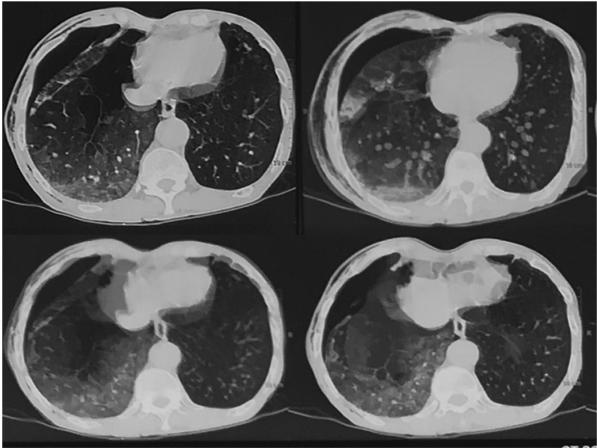

第二天进行高分辨率计算机断层扫描(HRCT)胸片检查,显示右侧气胸和肺水肿消失(图4)。继续保守治疗24h,患者病情继续改善2d,复查胸片显示右肺扩张和肺水肿消退。持续给予NIV和肌力支持48h,同时给予高流量氧治疗。6天后,ICD的漏气停止。ICD取出,观察1天后出院,建议戒烟并继续使用支气管扩张剂。随访1个月和6个月,呼吸储备良好,无气胸复发。

图4 24小时后胸部HRCT显示肺水肿和气胸消退